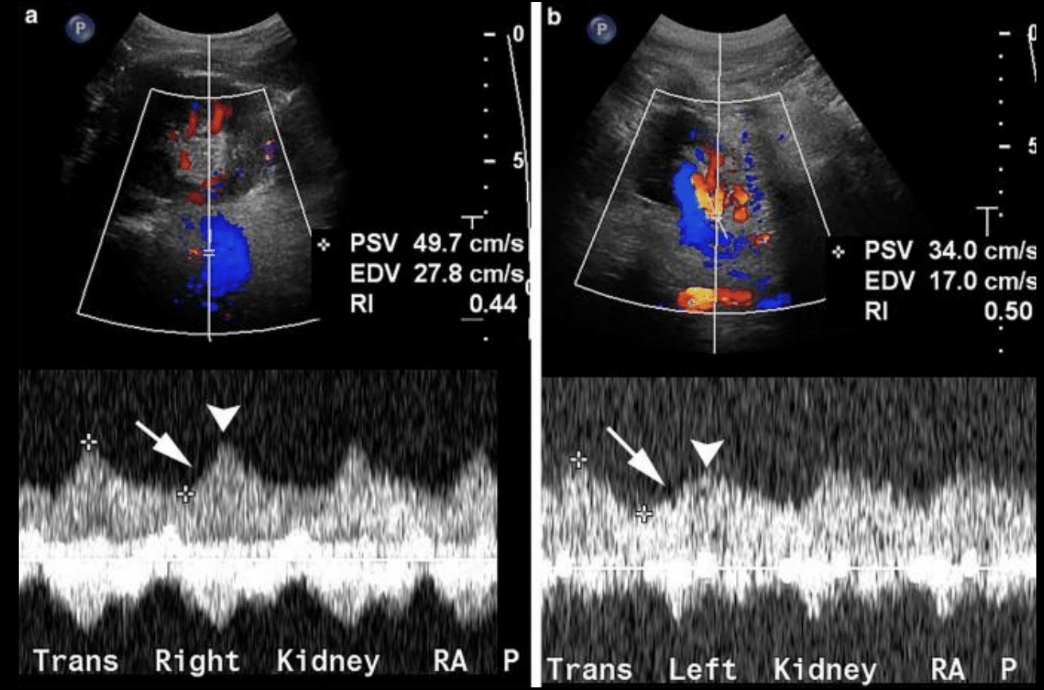

Doppler en renal

Estenosis e hipertensión renal